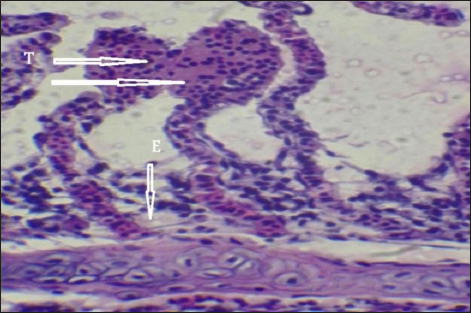

Histopathological findings of gill section showed telangictatisis and epithelial lifting in secondary lamellae (Fig. 7) with hemorrhage and blood congestion (Fig. 8), also, the result showed the central venous dilation with blood congestion and epithelium hyperplasia with complete fusion of the secondary lamellae (Figs. 9 and 10) and edema in the filamentary epithelium (Fig. 11) in addition to mononuclear cells infiltration (Figs. 12 and 13).

Fig. 7. Histopathological sections of gill of C. carpio showing telangictatisis (T) and epithelial lifting (EPL) (H&E X10).

The changes in gill tissue are not exclusive to As, Pb, and Hg toxicity (e.g., telangiectasis, epithelial lifting, hemorrhage, congestion, etc.) which have been previously reported in other stressful situations, like pesticide exposure (Fanta et al., 2003). All of these changes may be defense mechanisms meant to lengthen the time it takes for waterborne contaminants to diffuse and enter the bloodstream (Arellano et al., 1999). With particular reference to exposure to metals, Mustafa et al. (2012) observed telangiectasis, necrosis, in mirror carp C. carpio exposed to Cu, with the epithelium lifted away from the basement membrane. Similar results were also noted in Sole senegalensis, the Senegalese sole, after it was exposed to a sub-lethal concentration of Cu for 7 days (Arellano et al., 1999).